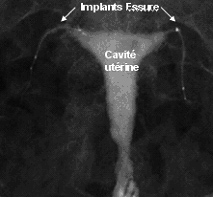

En cas de doute, une hystérosalpingographie (radiographie de l’utérus et des trompes) peut être prescrite par votre chirurgien afin de vérifier l’obstruction des trompes (Figure 4).

(Figure 4)